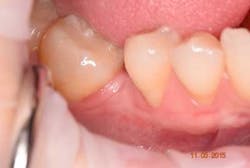

Plaque control after surgery was maintained using a very soft brush, avoiding the surgical side for one week and also using a PerioSciences antioxidant gel. No periodontal dressing was used. Healing was uneventful, and the patient did not have discomfort after one week post-operatively (figure 7).

The patient demonstrated excellent healing one month post-operatively (figure 8) with a significant increase in keratinized tissue. This increase in soft tissue will aid in the prevention of further recession during orthodontic therapy (figure 9) as well as assist in the coronal advancement of tissue post orthodontic therapy for the purposes of root coverage. Most importantly, the patient was extremely happy with the result.